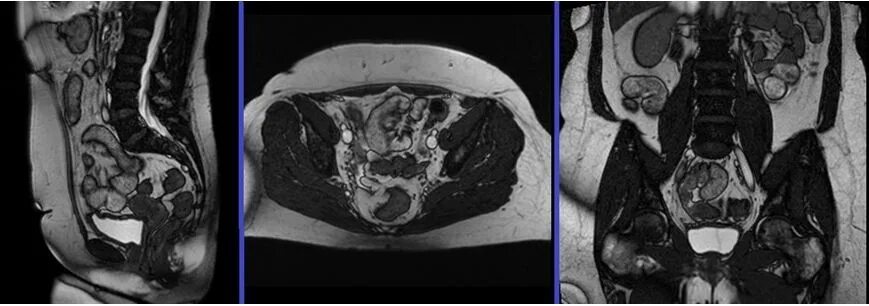

Мрт большого таза